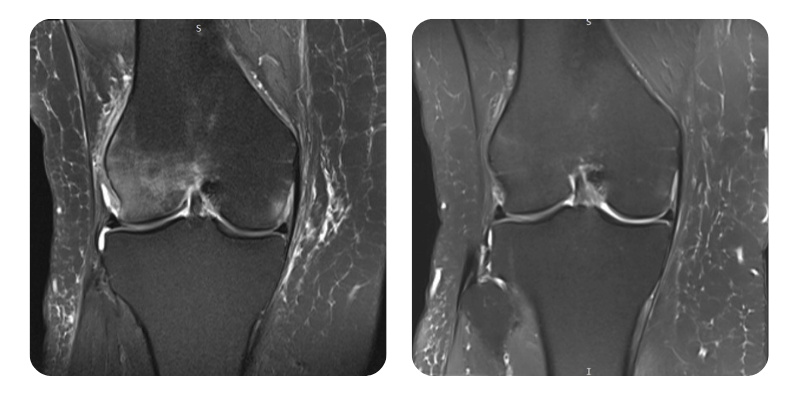

Vorher

Nachher

S.M.S., 58 Jahre – Nekrose/Ödem des lateralen rechten Femurkondylus

Diagnose: Nekrose/Ödem des lateralen rechten Femurkondylus, Zustand nach Vorhofflimmern mit Ablation, aktuell Sinusrhythmus, arterielle Hypertonie, Divertikulose.

Verlauf: Im MRT zeigt sich eine Ödemreduktion von ca. 90%.